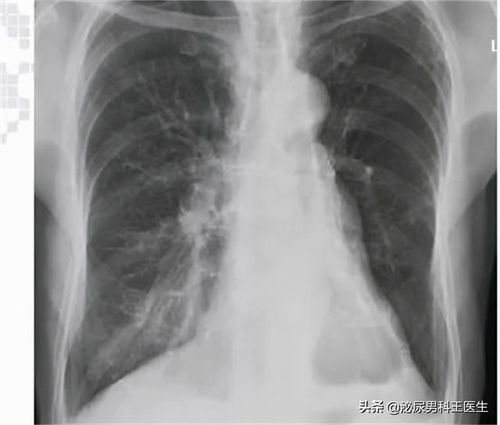

在心脏造影的神奇世界时,有一个缩写“PL”经常出现在我们的视野中。它代表着左室后支(Posterior Lateral Artery),是心脏冠状动脉中的一个重要分支。今天,让我们一起揭开它的神秘面纱,了解它在心脏中的功能与重要性。

在复杂的冠脉系统中,“PL”即左室后支,是右冠状动脉(RCA)的一个重要分支。它位于心脏的结构深处,专门负责为心脏左室的后侧壁提供血流。

心脏造影是一种用于检查心脏血管健康的诊断工具。在造影过程中,“PL”这一缩写代表了左室后支,是医生关注的重点之一。通过对左室后支的仔细观察,医生可以评估其形态、血流状况以及是否存在狭窄或堵塞等问题。这些信息的获取对于准确判断心脏功能至关重要。